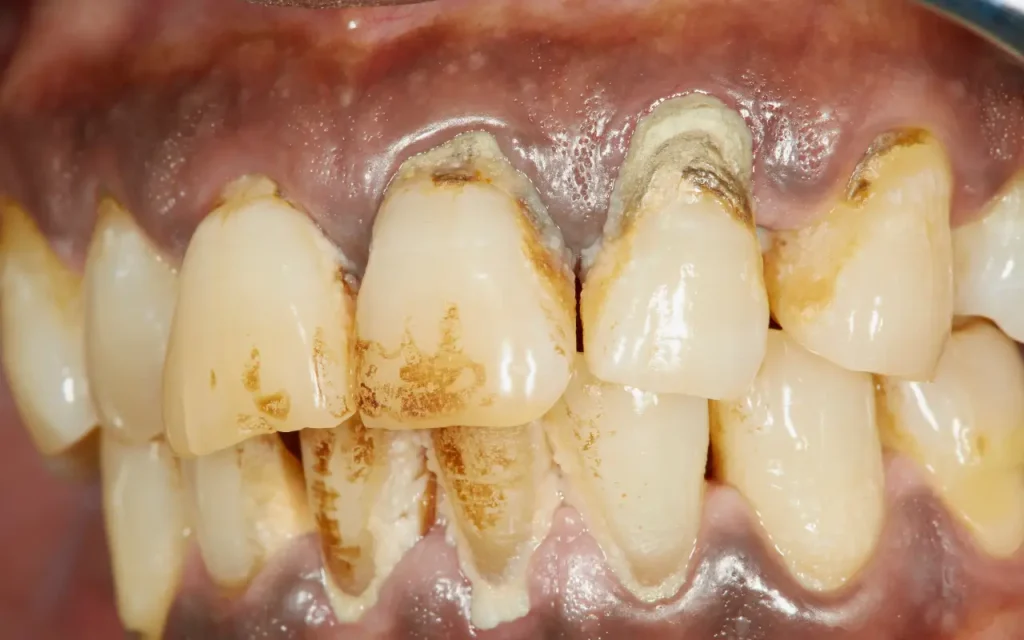

โรคปริทันต์อักเสบ (Periodontal disease) หรือ ที่ภาษาท้องถิ่นเรียกว่าโรครำมะนาด คือ โรคที่มีการอักเสบและการทำลายของอวัยวะปริทันต์ ซึ่งได้แก่ เหงือก เคลือบรากฟัน เอ็นยึดรากฟัน และกระดูกเบ้าฟัน อวัยวะเหล่านี้จะถูกทำลายไปอย่างช้าๆ จนทำให้เกิดอาการฟันโยก จนในที่สุดฟันก็จะหลุดไป

คือภาวะที่ลุกลามและ รุนแรงกว่า โดยการอักเสบไม่ได้จำกัดอยู่แค่ที่เหงือกอีกต่อไป แต่ได้แพร่กระจายลึกลงไปทำลาย อวัยวะรอบรากฟัน เช่น เหงือก เอ็นยึดปริทันต์ เคลือบรากฟัน กระดูกเบ้าฟัน อาการจึงรุนแรงขึ้นอย่างเห็นได้ชัด เช่น เหงือกร่นจนเห็นรากฟัน มีหนองไหลซึมจากร่องเหงือก มีกลิ่นปากรุนแรง และฟันเริ่มโยกคลอน หากเป็นมากๆ อาการรุนแรงจะไม่สามารถรักษาให้กลับคืนมาเหมือนเดิมได้ ทำได้เพียงถอนฟันหรือควบคุมโรคไม่ให้ลุกลามไปมากกว่านี้เท่านั้น

โรคปริทันต์นั้นเกิดจากเชื้อแบคทีเรีย โดยเริ่มต้นจากการสะสมของเศษอาหารและคราบจุลินทรีย์อยู่บนฟัน ประกอบกับการทำความสะอาดฟันที่ไม่ดีพอ เมื่อมีการสะสมแบคทีเรียมากขึ้น แบคทีเรียจะมีการทำลายกระดูกและฟันบริเวณนั้น ร่างกายก็จะสร้างสารขึ้นมาต่อสู้กับเชื้อโรค แต่ในทางกลับกันสารที่ร่างกายปล่อยออกมาก็จะทำลายกระดูกและฟันที่อยู่รอบๆ ด้วย เมื่อเวลาผ่านไประยะหนึ่งทั้งฟันและเหงือกก็จะโดนทำลายจนกลายเป็นโรคปริทันต์

- ตรวจสุขภาพช่องปาก ประเมินคราบจุลินทรีย์ คราบหินปูน ประเมินลักษณะเหงือกว่ามีการอักเสบกี่ตำแหน่ง มีเลือดออกง่ายหรือไม่ สีเหงือกเป็นอย่างไร รูปร่างและความแน่นของเหงือก